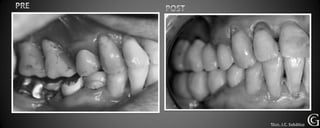

PRE

Prótesis Fija Convencional

Puentes

Los puentes son restauraciones que sirven para reemplazar piezas

perdidas, involucrando piezas vecinas. Son confeccionadas fuera

de la boca y luego adheridas o cementadas a los dientes vecinos a

a la pieza perdida.

PRE Técn. R. Schaeffer

Prótesis Fija Convencional Puentes Los puentes son restauraciones que sirven para reemplazar piezas perdidas, involucrando piezas vecinas. Son confeccionadas fuera de la boca y luego adheridas o cementadas a los dientes vecinos a a la pieza perdida.